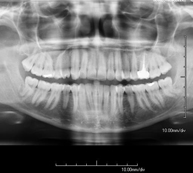

- RX Crani

Tècnica que usa els raigs X a través de la qual s'obtenen imatges del crani per al seu estudi. Indicacions: traumatisme, tancament precoç de sutures cranials. - RX Sins Paranasals